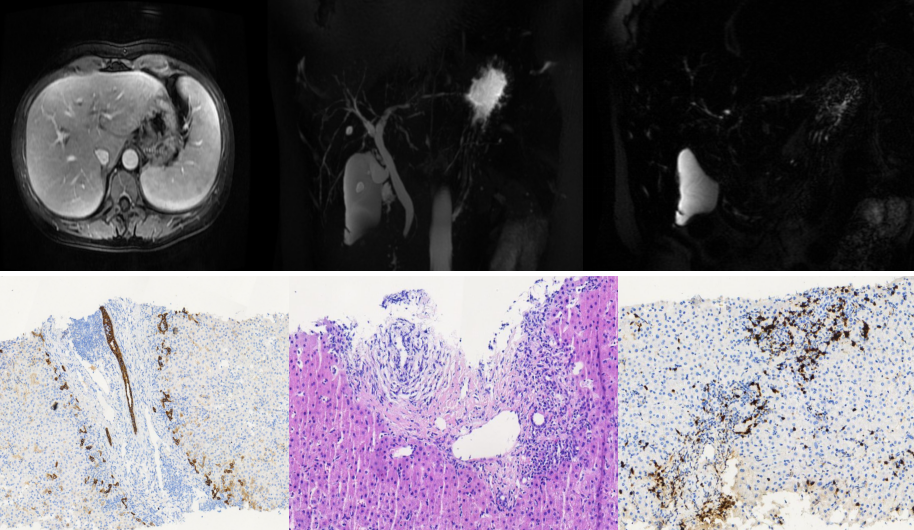

肝肿瘤穿刺活检:考虑肝细胞肝癌(低分化)

对比患者的磁共振片,胡海与团队成员反复推演,确定患者肝脏,胆囊等

胆囊床与肝脏贴和面小,结石紧贴胆囊壁,手术难度较大超声引导下穿刺及